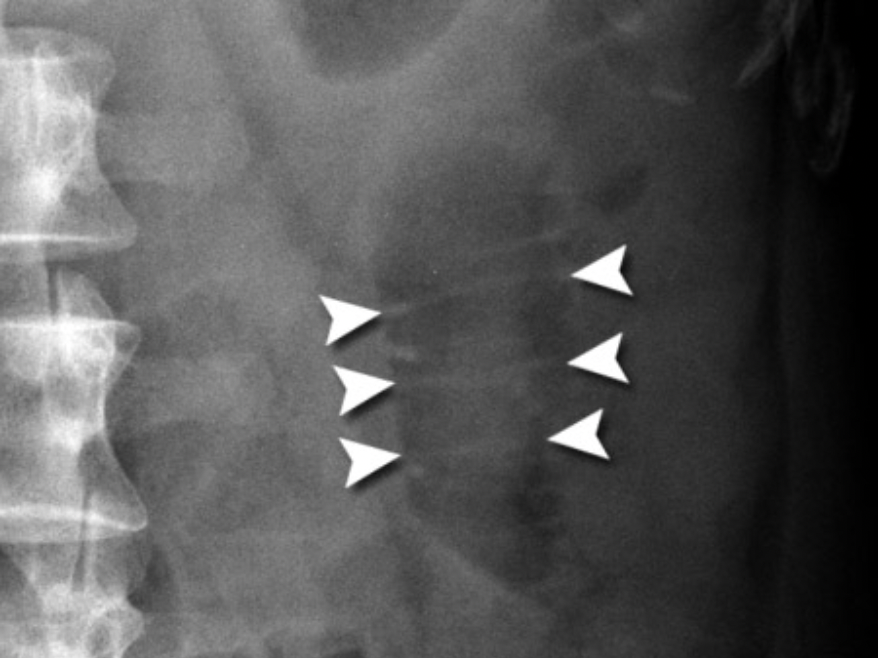

Label the structures

Top left → liver edge

Bottom left → kidney

Top right → spleen

Middle right → stomach

Bottom right → psoas